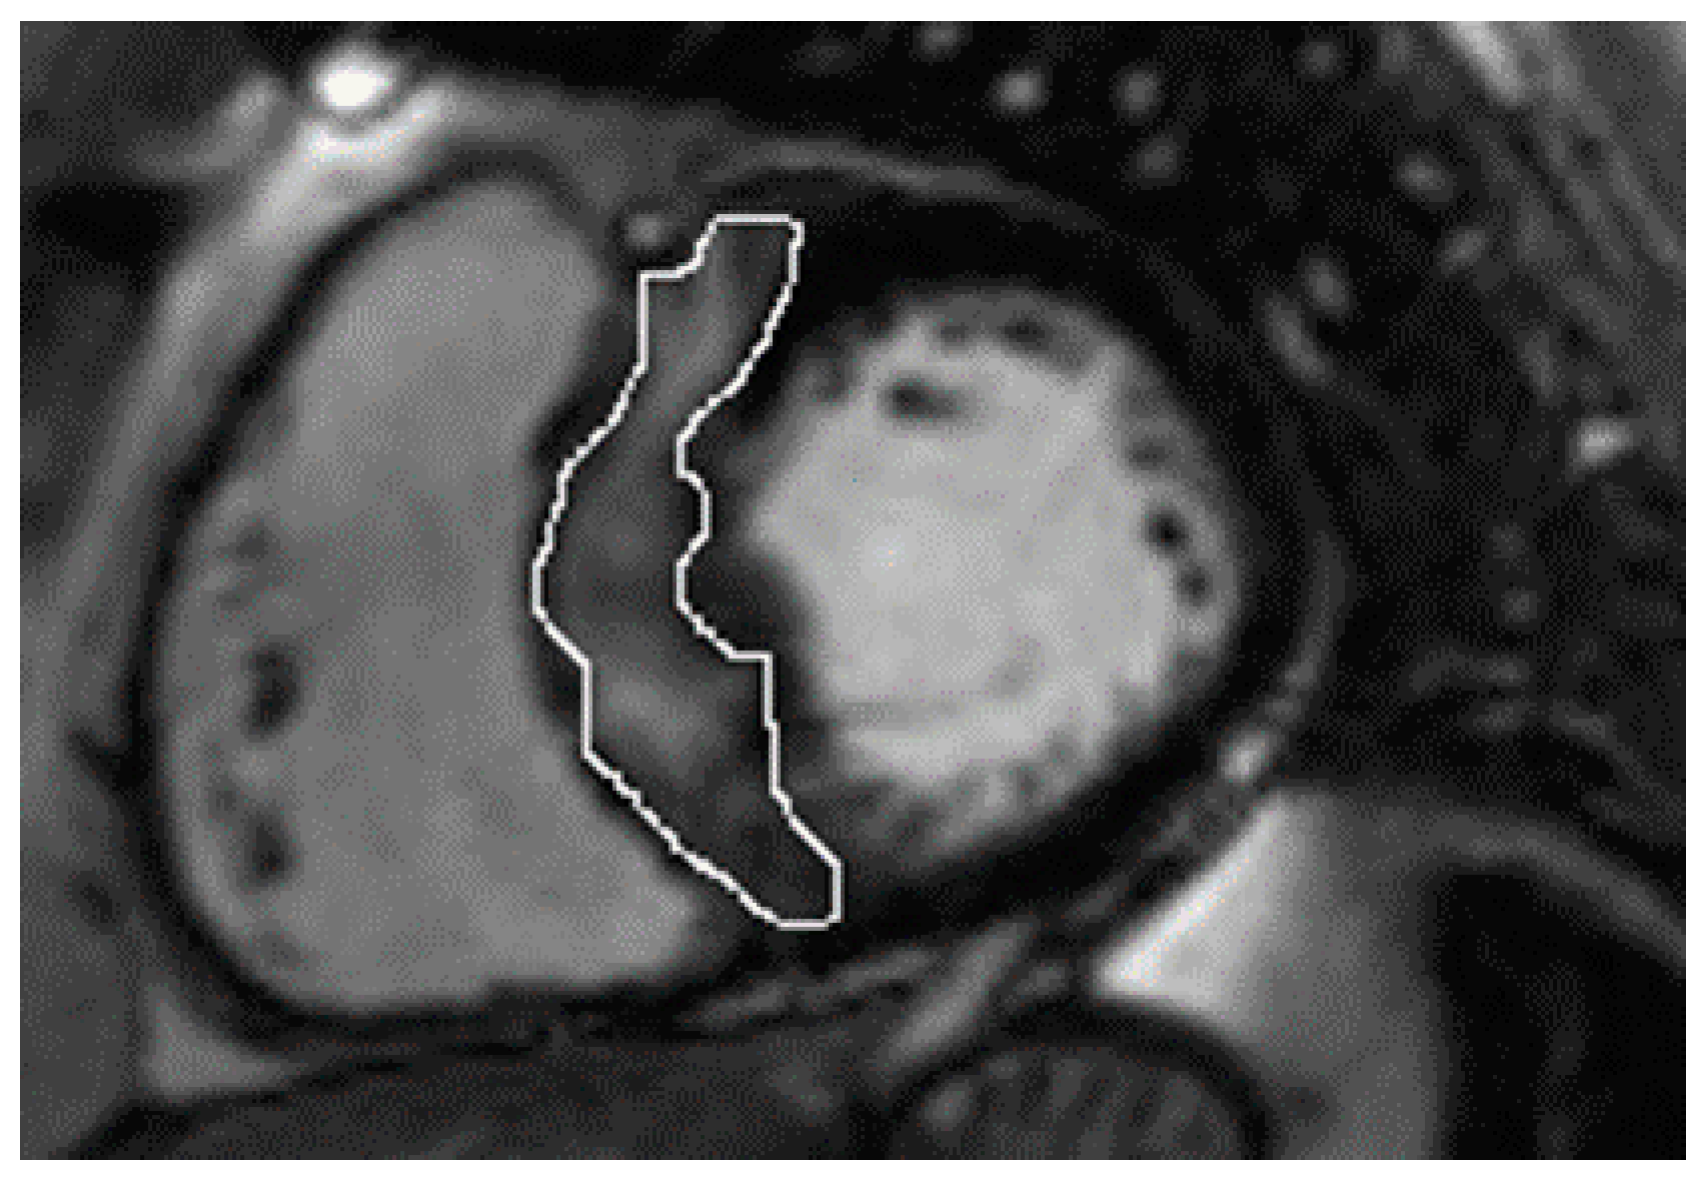

In the whole group, LGE was present in 37 (74%) patients. Patients with nsVT had a larger extent with respect to LGE (Table 2). However, the patients did not differ in native and post-contrast T1 times and ECV values, and the mere presence of LGE only showed a trend towards significance. Figure 1 and Figure 2 present examples of images obtained in the CMR studies.

Figure 1.

Late gadolinium enhancement (LGE) images show the quantification of the septal burden of replacement fibrosis (circled) via the technique which uses a 5-standard-deviations threshold on consecutive short-axis slices.